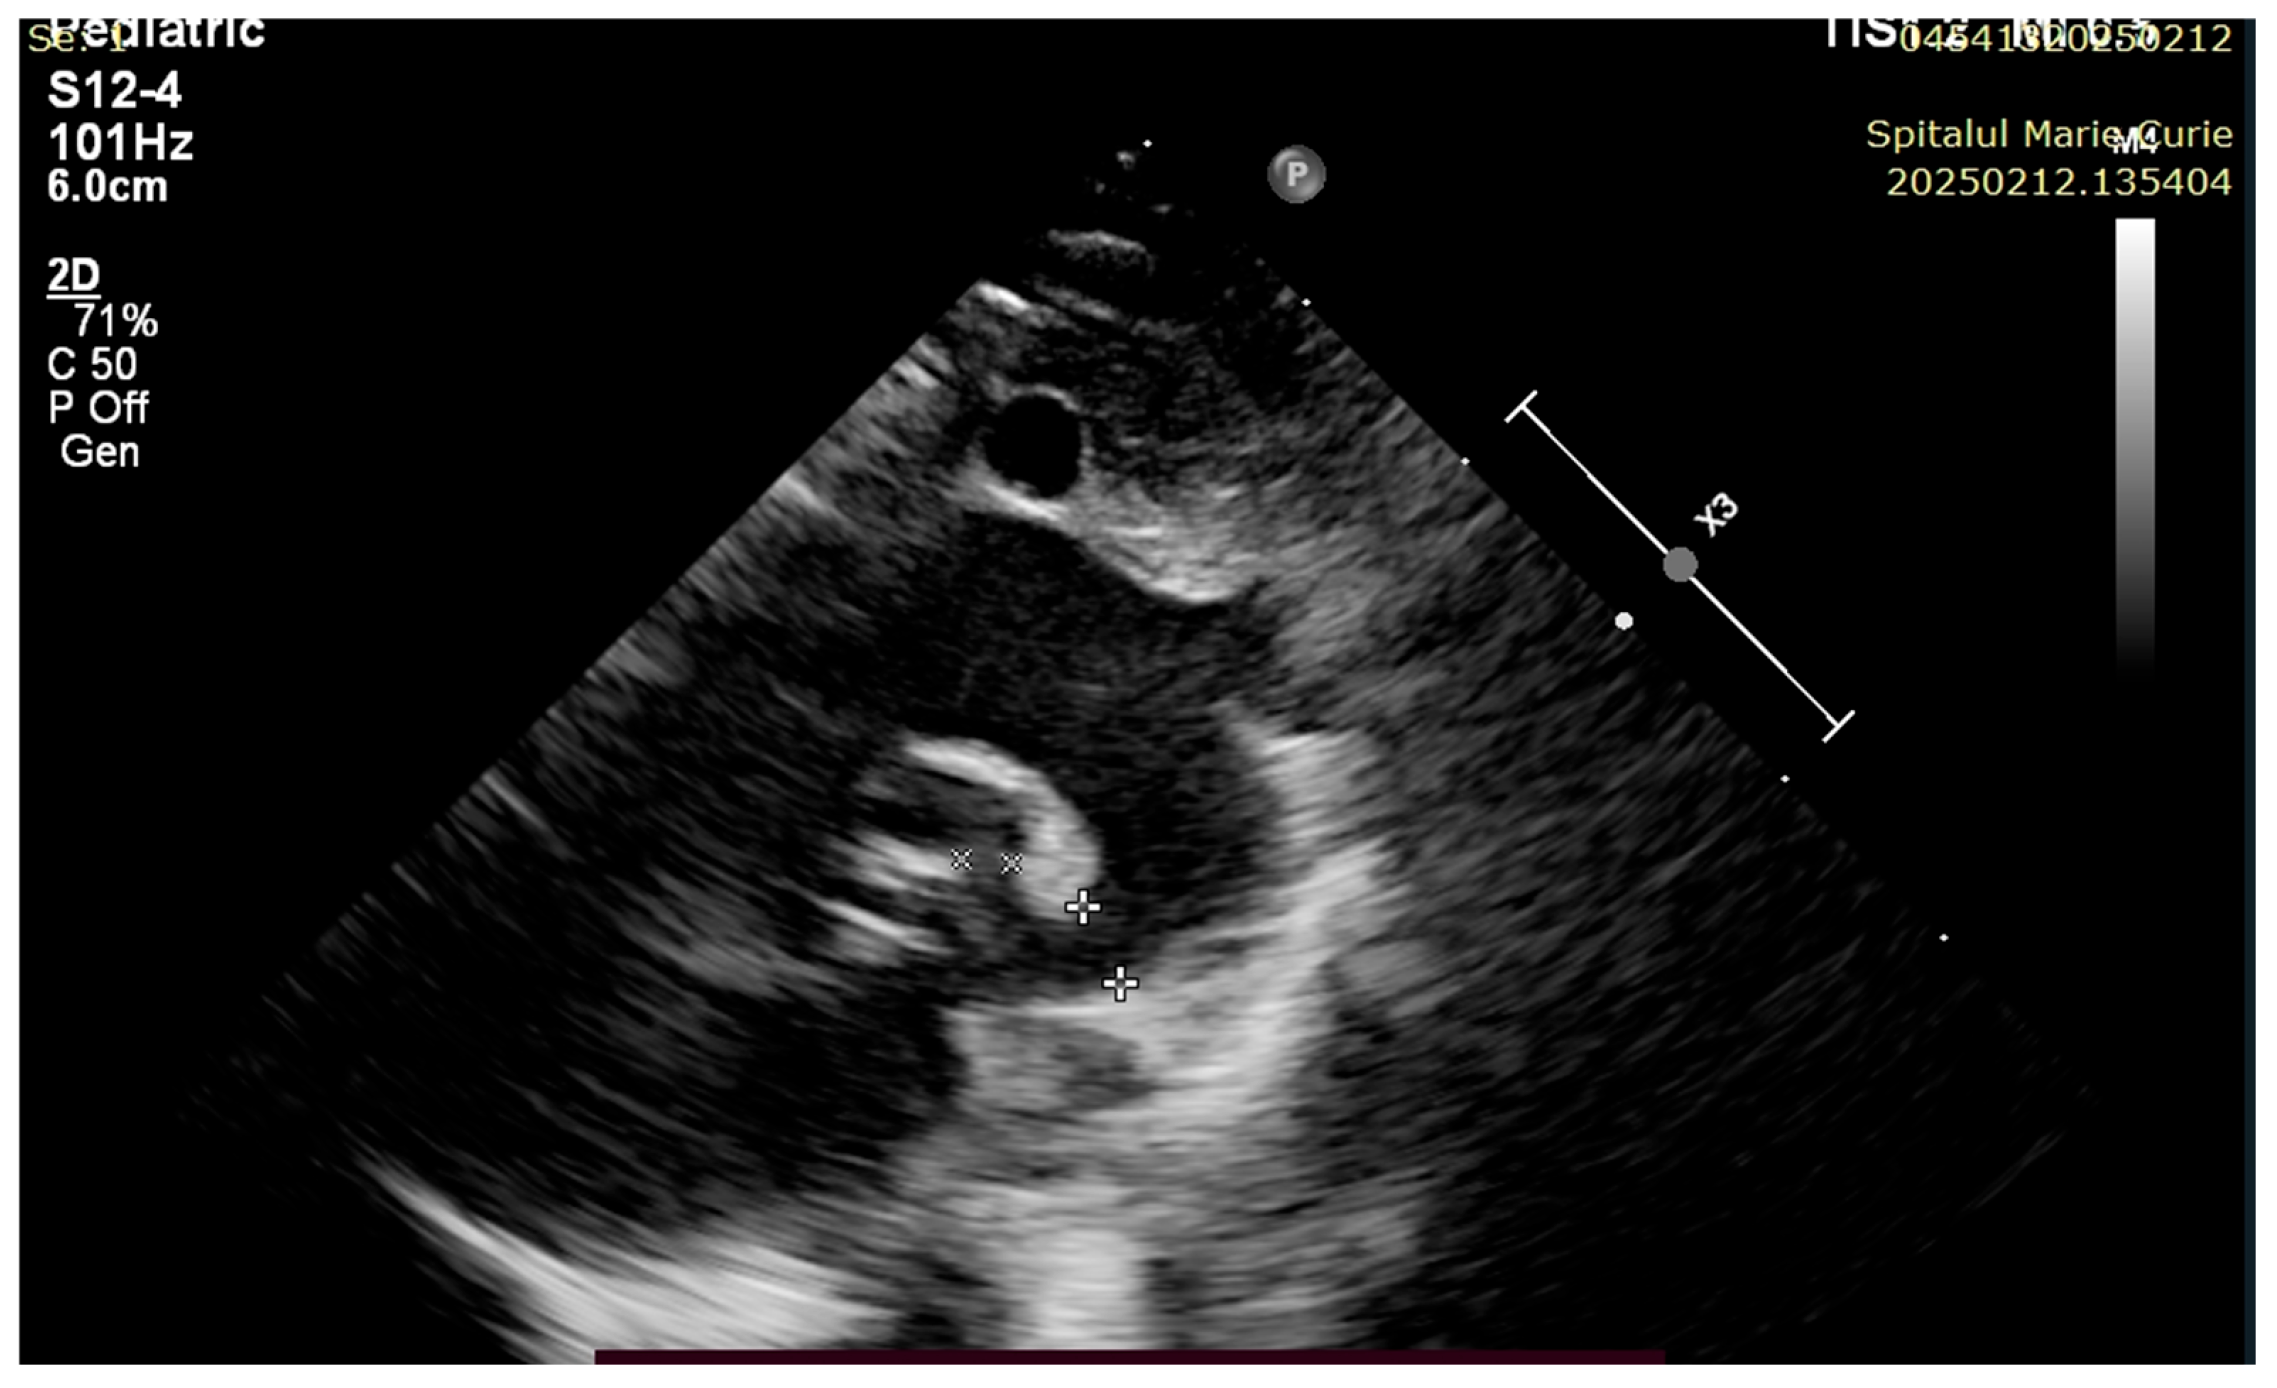

4. Case Reports